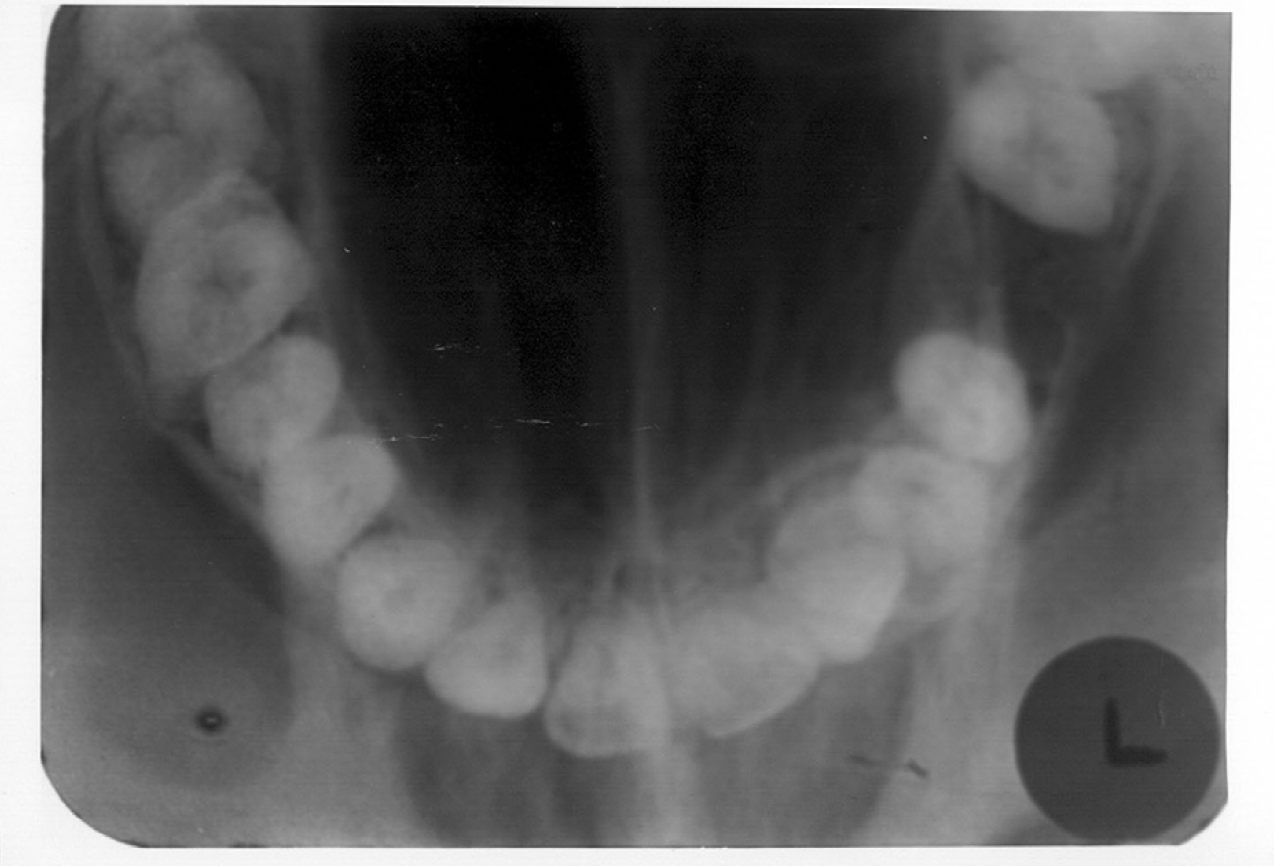

A fourteen or sixteen intraoral periapical survey, as seen in Figure 7, will usually examine the tooth bearing regions in most edentulous patients. Bitewings are not needed because there are no interproximal areas to be examined.

Figure 7 - Edentulous Full Mouth Series

Figure 7